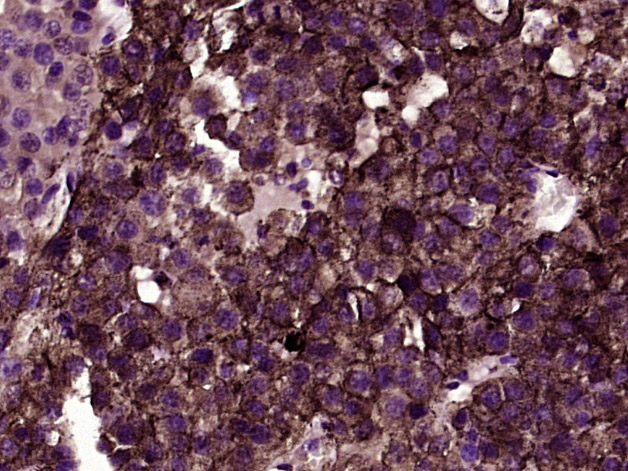

Paraformaldehyde-fixed, paraffin embedded (Human melanoma); Antigen retrieval by boiling in sodium citrate buffer (pH6.0) for 15min; Block endogenous peroxidase by 3% hydrogen peroxide for 20 minutes; Blocking buffer (normal goat serum) at 37°C for 30min; Antibody incubation with (NG2) Polyclonal Antibody, Unconjugated (bs-23788R) at 1:400 overnight at 4°C, followed by operating according to SP Kit(Rabbit) (sp-0023) instructionsand DAB staining.